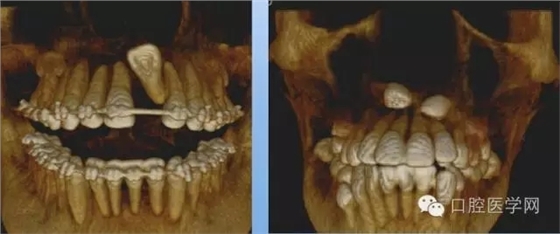

3.牙齒數(shù)目異常

額外牙

X線表現(xiàn):最多見于上頜兩中切牙之間;圓錐形,根短小;拍攝X線片可確定額外牙的數(shù)目、位置、形態(tài)與鄰牙的關(guān)系。